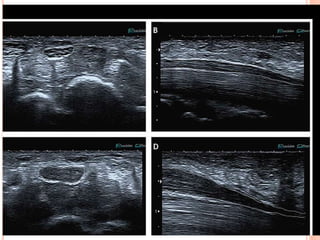

 Normal peripheral nerves have a tubular form, with

alternating hypoechoic (nerve fibers) and

hyperechoic (perineurium) zones that give the

impression of a honeycomb pattern

1-INFORMATION ABOUT PLAQUECOMPOSITION AND SURFACE  Cervical duplex ultrasonography can directly visualize atherosclerotic plaque composition that can be classified based on its echogenicity.  Uniformly hyperechoic carotid plaques are mainly composed of fibrotic tissue needed for plaque stability.  In contrast, heterogeneous (and predominantly hypoechoic) plaques consisting of matrix deposition, cholesterol accumulation, necrosis, calcification, and intraplaque hemorrhage are considered unstable, being the source of artery-to-artery embolic strokes